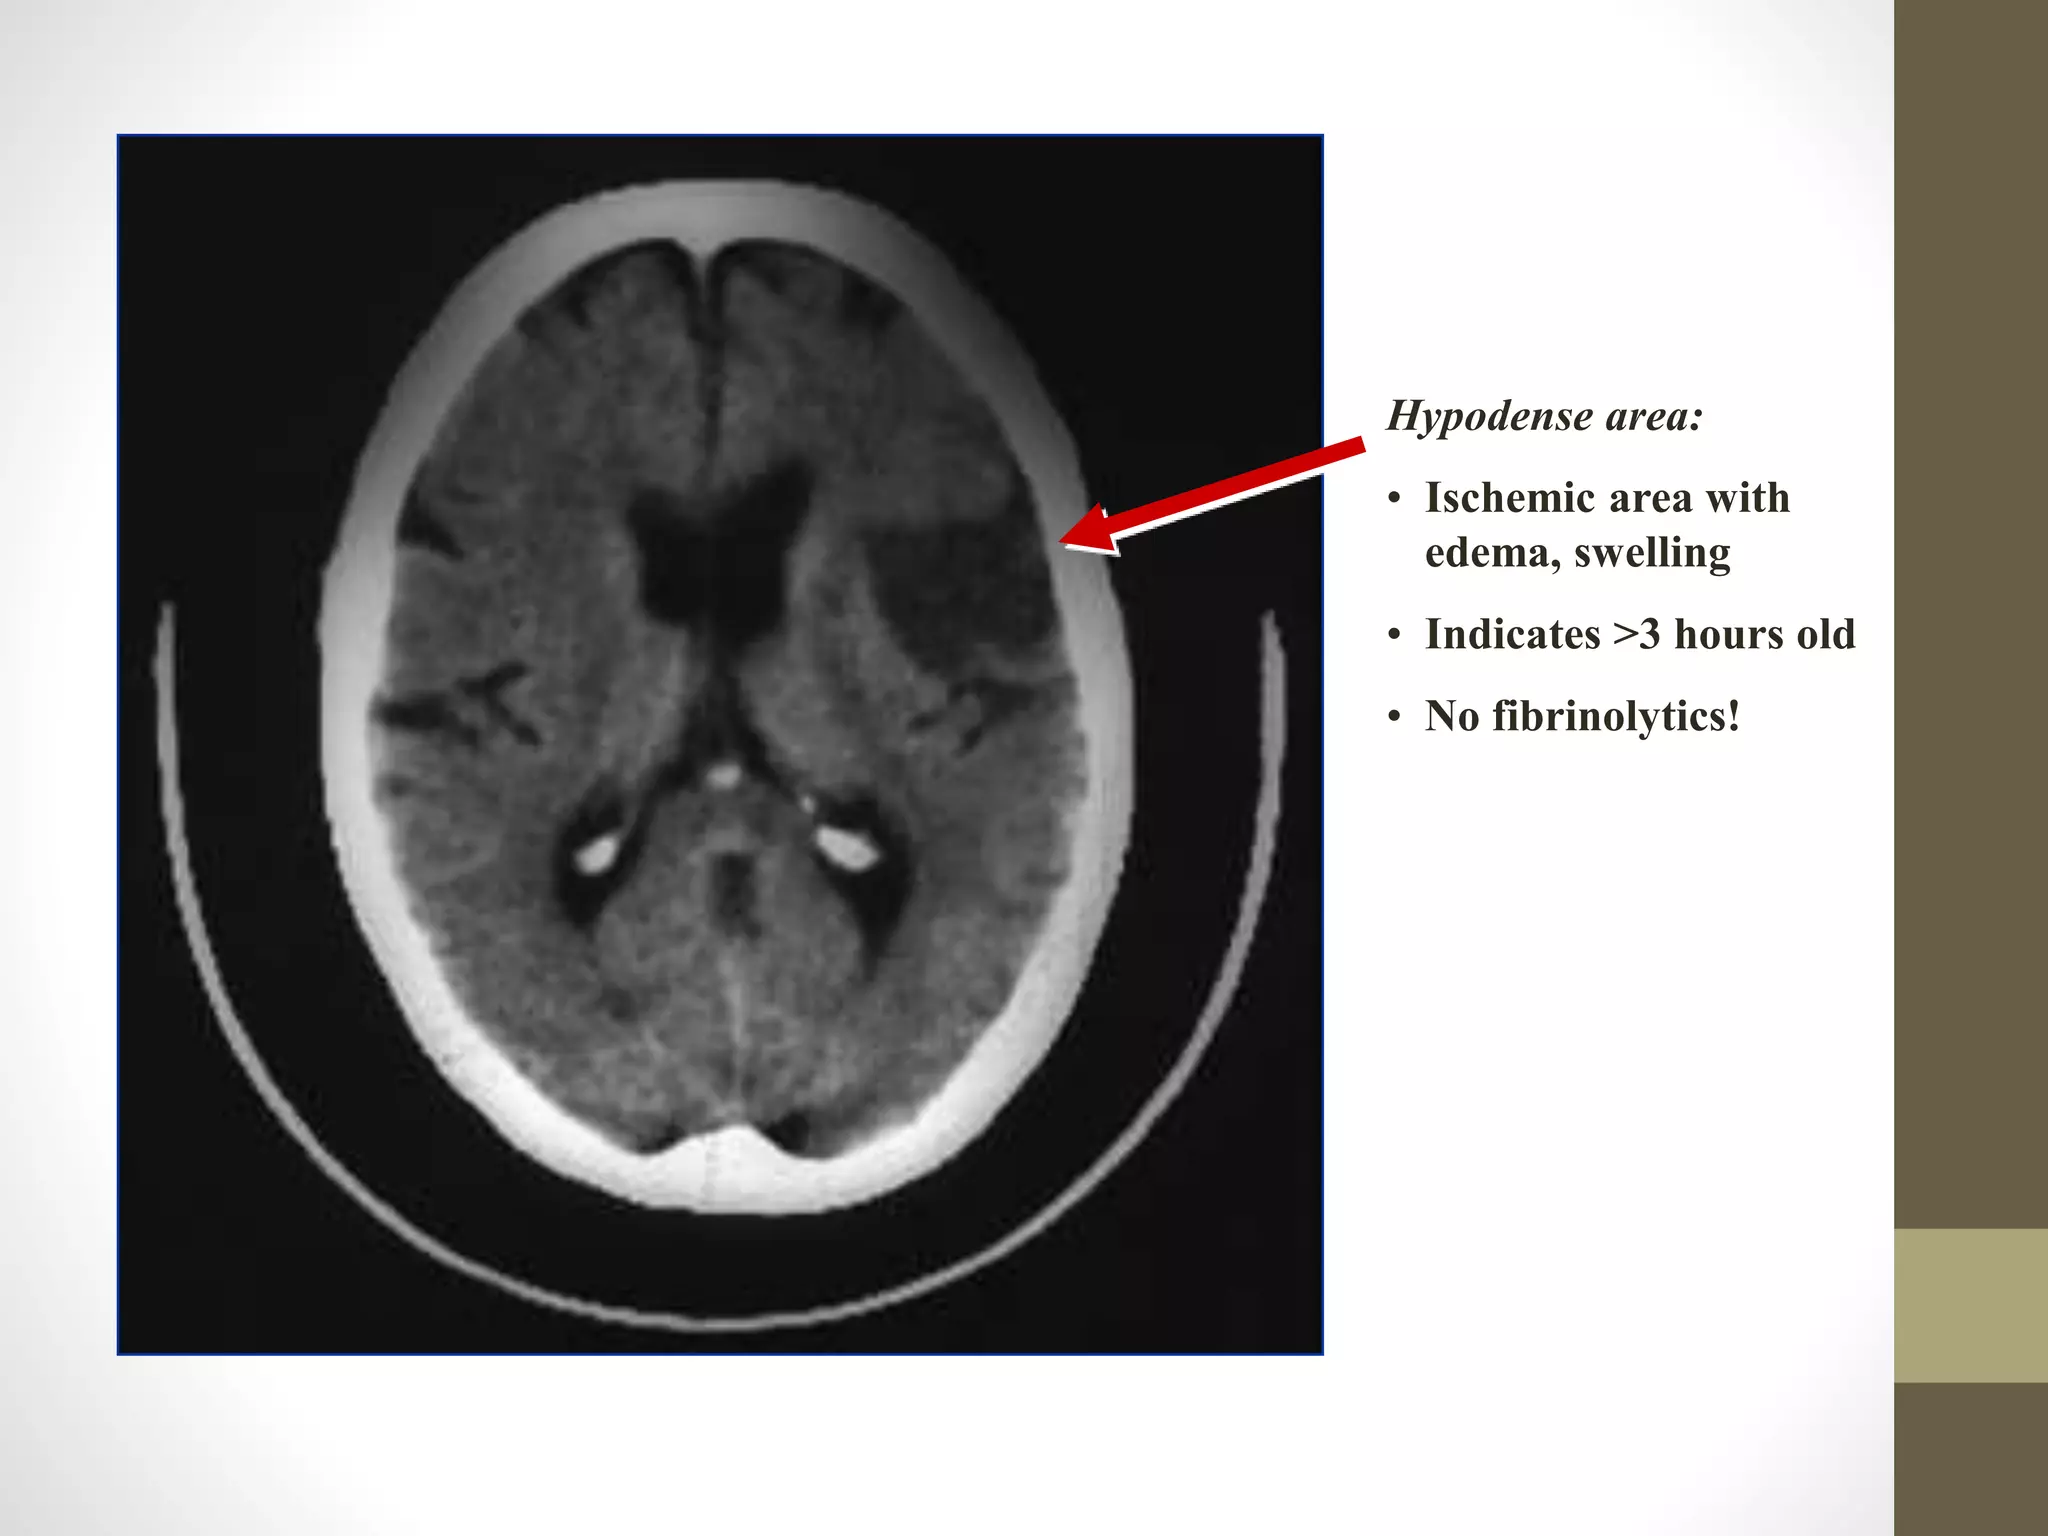

Hypodense area:

• Ischemic area with

edema, swelling

• Indicates >3 hours old

• No fibrinolytics!

Hypodense area: • Ischemicarea with edema, swelling • Indicates >3 hours old • No fibrinolytics!